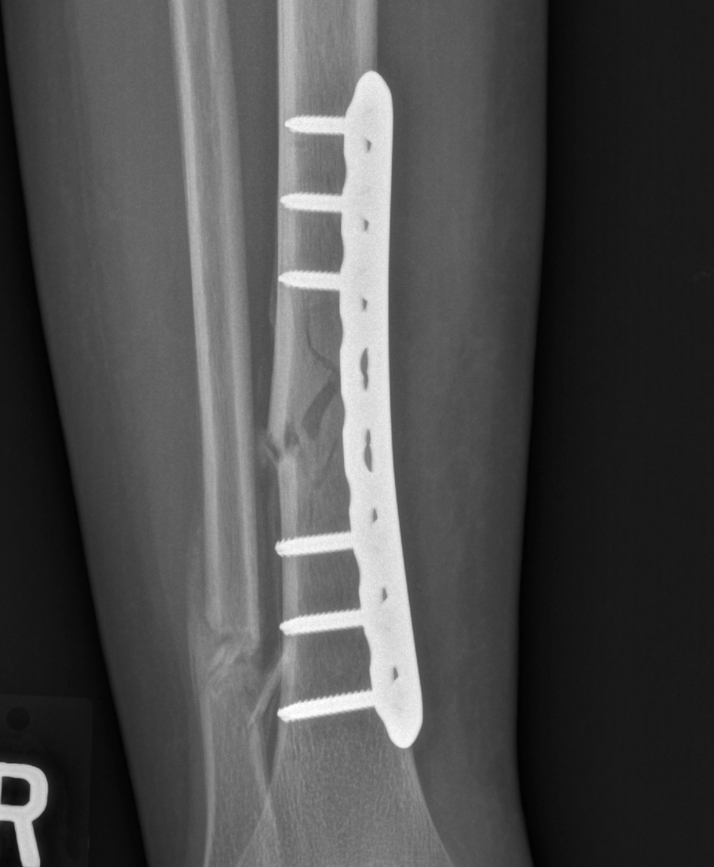

Info Images Findings Impression Reco/Acuity Case Images View Images / Launch Visage Case Notes History 2-month-old presents with decreased right arm movement, increased fussiness, and increased sleepiness for 2 days. Suspected non-accidental trauma. Exam Skeletal survey Prior Study none Dicom View Reference Material

Section 1 Submit Findings CB1550 Findings Skeletal Survey - Technique Check Skull AP/Lat Yes No Cervical and Thoracolumbar spine Yes No Chest X-Ray Yes No Ribs – Left/Right Oblique Yes No Abdominal X-Ray Yes No Pelvis with both hips Yes No Bilateral Humerus, Forearm, Hand Yes No Bilateral Femur, Tibia/fibula, feet Yes No Any additional lateral views of the extremities Yes No The exam is over or under penetrated. Yes No The exam may or may not be limited by overlying structures or soft tissues, body habitus, patient positioning, support devices, or motion. Yes No The area of concern is indicated by the patient, technologist, or care provider. Yes No The area of concern is included on the exam. Yes No Soft Tissues There is soft tissue swelling, indistinctness of fat/muscle planes, gas, or laceration in the area of clinical concern. Yes No There is an effusion, fat pad displacement, or fat fluid level. Yes No There is a radiodense or lucent foreign body. Yes No There are other densities, calcifications, post-surgical changes, or support devices in the soft tissues. Yes No Any support lines/tubes. Yes No Bone There is a break or interruption of the continuity of the cortical or cancellous bone. Yes No There is overriding of the trabeculae with apparent sclerosis. Yes No There is displacement of a fracture fragment. Yes No There is bowing of the bone in addition to the fracture at the apex of the bowed bone concerning for the greenstick. Yes No There is a spiral fracture of the leg concerning for toddler’s fracture. Yes No There is abnormal angulation or bulging of the cortical surface relative to the normal cortex which could be from a buckle or torus fracture. Yes No There is a displaced fragment which may be from avulsion by a tendon, ligament, or joint capsule or from a comminuted or other fracture. Yes No The stress trabeculae or other trabeculae of the cancellous bone are interrupted or otherwise abnormal. Yes No There is subperiosteal or endosteal reaction which could indicate a healing or subacute fracture or other abnormality. Yes No There is hard/soft callus formation. Yes No There is remodeling of the bone. Yes No There is a corner fracture or metaphyseal lesion that could be from nonaccidental trauma. Yes No There are multiple fractures of different ages. Yes No There are vertebral body/spinous process fractures. Yes No There are rib fractures. Location - posterior or lateral. Yes No There is scapular/sternal fracture. Yes No There are fractures of the digits. Yes No There are wormian bones. Yes No There are intrasutural bones. Yes No There is metaphyseal abnormality (lucencies, increased density, erosion) which may be from something other than injury such as stress, metabolic disease (e.g. rickets with loss or distortion of the zone of the provisional calcification), neoplasm (e.g. leukemia), heavy metals, inflammation, or infection. Yes No There are metaphyseal spurs. Yes No There are bony deformities involving multiple bones. Yes No The bones are gracile. Yes No There are non-healing fractures. Yes No There is/are focal or multifocal lytic/lucent, blastic/sclerotic or mixed density lesion(s) or other abnormality. Yes No Overall bone density is increased or decreased with or without thinning or thickening of the cortical or cancellous bone. Yes No Growth plates, ossification centers, apophyses The growth plate(s) is/are abnormal. Yes No There is widening of the physis from a fracture with or without displacement of the epiphysis (Salter-Harris I). Yes No There is a fracture through the physis which then extends into the metaphysis with or without angulation or displacement (S-H II). Yes No There is a fracture through the physis which then extends into the epiphysis and is intra-articular, with or without angulation or displacement (S-H III). Yes No There is a fracture through the metaphysis, physis, and epiphysis which extends into the joint space with or without angulation or displacement (S-H IV). Yes No There is narrowing of the physis from a compression fracture (S-H V). Yes No The apophysis, epicondyle, secondary ossification center, or accessory ossicle is displaced or otherwise abnormal. Yes No The ossification centers are underdeveloped. Yes No Joints and alignment There is an effusion, fat pad displacement, or fat fluid level. Yes No The epiphysis or subchondral bone is fractured, interrupted, flattened, compressed, impacted, displaced, or otherwise abnormal. Yes No There is an intra-articular loose body or chondrocalcinosis. Yes No The joint is widened, narrowed, dislocated, malaligned, or incongruent. Yes No There is pseudoarthrosis. Yes No Other findings There are developmental changes or other anatomic variants or other existing conditions that may or may not be contributing to symptoms which can or should be further evaluated non-emergently or are otherwise incidental. Yes No The remainder of the exam is abnormal for age. Yes No The lungs show focal airspace opacity. Yes No There is pneumothorax. Yes No There is organomegaly. Yes No There is intra-abdominal calcification. Yes No There is displacement of the bowel loops. Yes No There is free intraperitoneal air. Yes No The bowel loops are dilated/obstructed. Yes No There is paraspinal soft tissue abnormality. Yes No